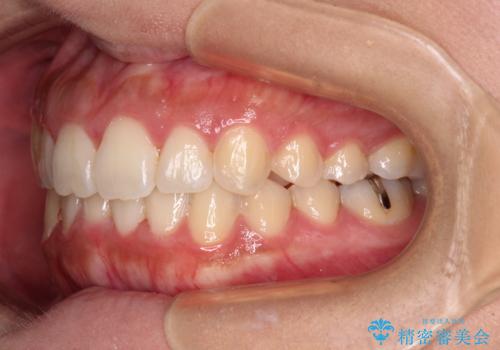

前歯のデコボコをインビザラインでスッキリと

- 上下前歯のデコボコを気にして来院された患者様です。

デコボコを解消する過程で、歯列の拡大により口元が突出する可能性があったため、4本の親知らずを抜歯しておき、歯列全体が後方に移動するように設計し、インビザラインにて矯正治療を行うこととしました。

日々の装着時間をしっかりと守って治療の臨んでくださったため、治療前のシミュレーションに近い形で矯正治療を進めて行くことができました。